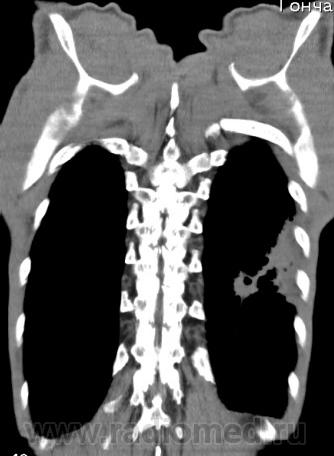

На фоне консолидации полость без содержимого. Может быть всё что угодно, что сопровождается деструкцией. Нужны ещё томограммы в лёгочном окне.

Изображения выставлены все. Ваше мнение уважаемые коллеги?

Туберкулёз.

Туберкулёз?

Это КТ 2-летней давности и попало оно мне в руки, после недавнего прохождения контроля пациентом, когда мы стали перед вопросом о специфическом / не специфическом процессе.

Тогда, пациента 2 месяца лечили от пневмонии, лечили интенсивности, стационарно, в серьёзном учреждении.

Предположу аспергиллез